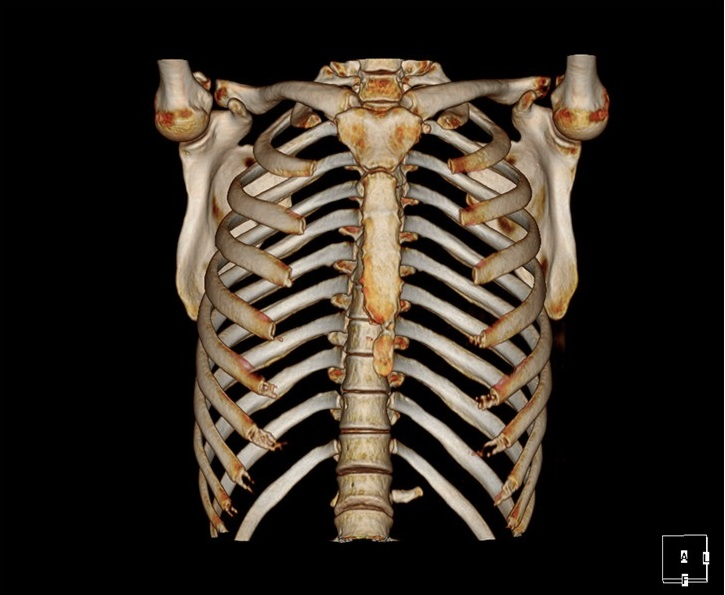

CT:像把西瓜切片看

CT的检查原理是X光会分层穿过人体,之后通过电脑计算后二次成像,就像把一个西瓜切成片来看。优点是可以分层看,经计算后可以显示出更多的组织信息。

CT是X线束围绕人体某部位一定厚度的层面进行扫描,后经计算机重建生成图像。CT的优势在于检查速度快,对于不配合的儿童要求低,易于完成检查。单部位CT检查只需两到三分钟即可完成。因此对于一些危重、急症疾病(如脑外伤、脑出血、外伤骨折等),CT应作为首选检查。胸部、骨骼的检查应选用CT检查。

CT检查还有一个优势就是利用CT扫描数据进行三维重建可以更直观的观察疾病,还可以为手术提供导航、3D打印技术,提高了手术的精确性。CT在进行扫描检查时是会产生一定的电离辐射的,但一次扫描的剂量是在安全范围内的,产生伤害的几率微乎其微,家长不必因担心而拒绝检查。